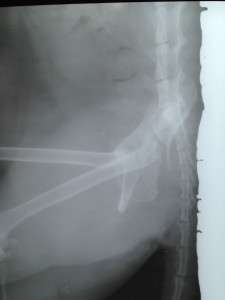

To save an animal does not mean to give a call or write a message and wait for the case to be solved. Unfortunately, many people think we are some sort of ANIMAL PLANET but in reality we make great efforts to cope with so many cases of accidents, abandonments, torture cases, especially since we don’t have a medical Office or veterinarian for the association; we go to medical offices where, through the goodwill of the doctors, we recieve discounts, but this does not mean there are no large costs and atferwards we take it upon ourselves to house the saved animal for life, regardless of the fact that it can remain with 2 or 3 legs, or blind for life. This is the way we transformed our home into a small sanctuary for nobody’s animals but now ours, and for this, many people think we receive money for these animals, because they are handicapped. False, many times we do not have enough to cover the medical bills, but after discharge we take them in and take responsibility for their care. This is how we received a phone call that a cat is lying unable to walk for some time, with her legs crushed, asking us to do something for her. So we did just that, we posted on social media asking for help with the transport to a clinic where we allready spoke for her. Fortunately, we found a person quickly and the poor kitty arrived at the clinic where she was hospitalized. But her state is very bad, a leg needs to be amputated and the spine is also fractured. But no matter if she remains with 3 legs or paralyzed, we will become her home from now on.